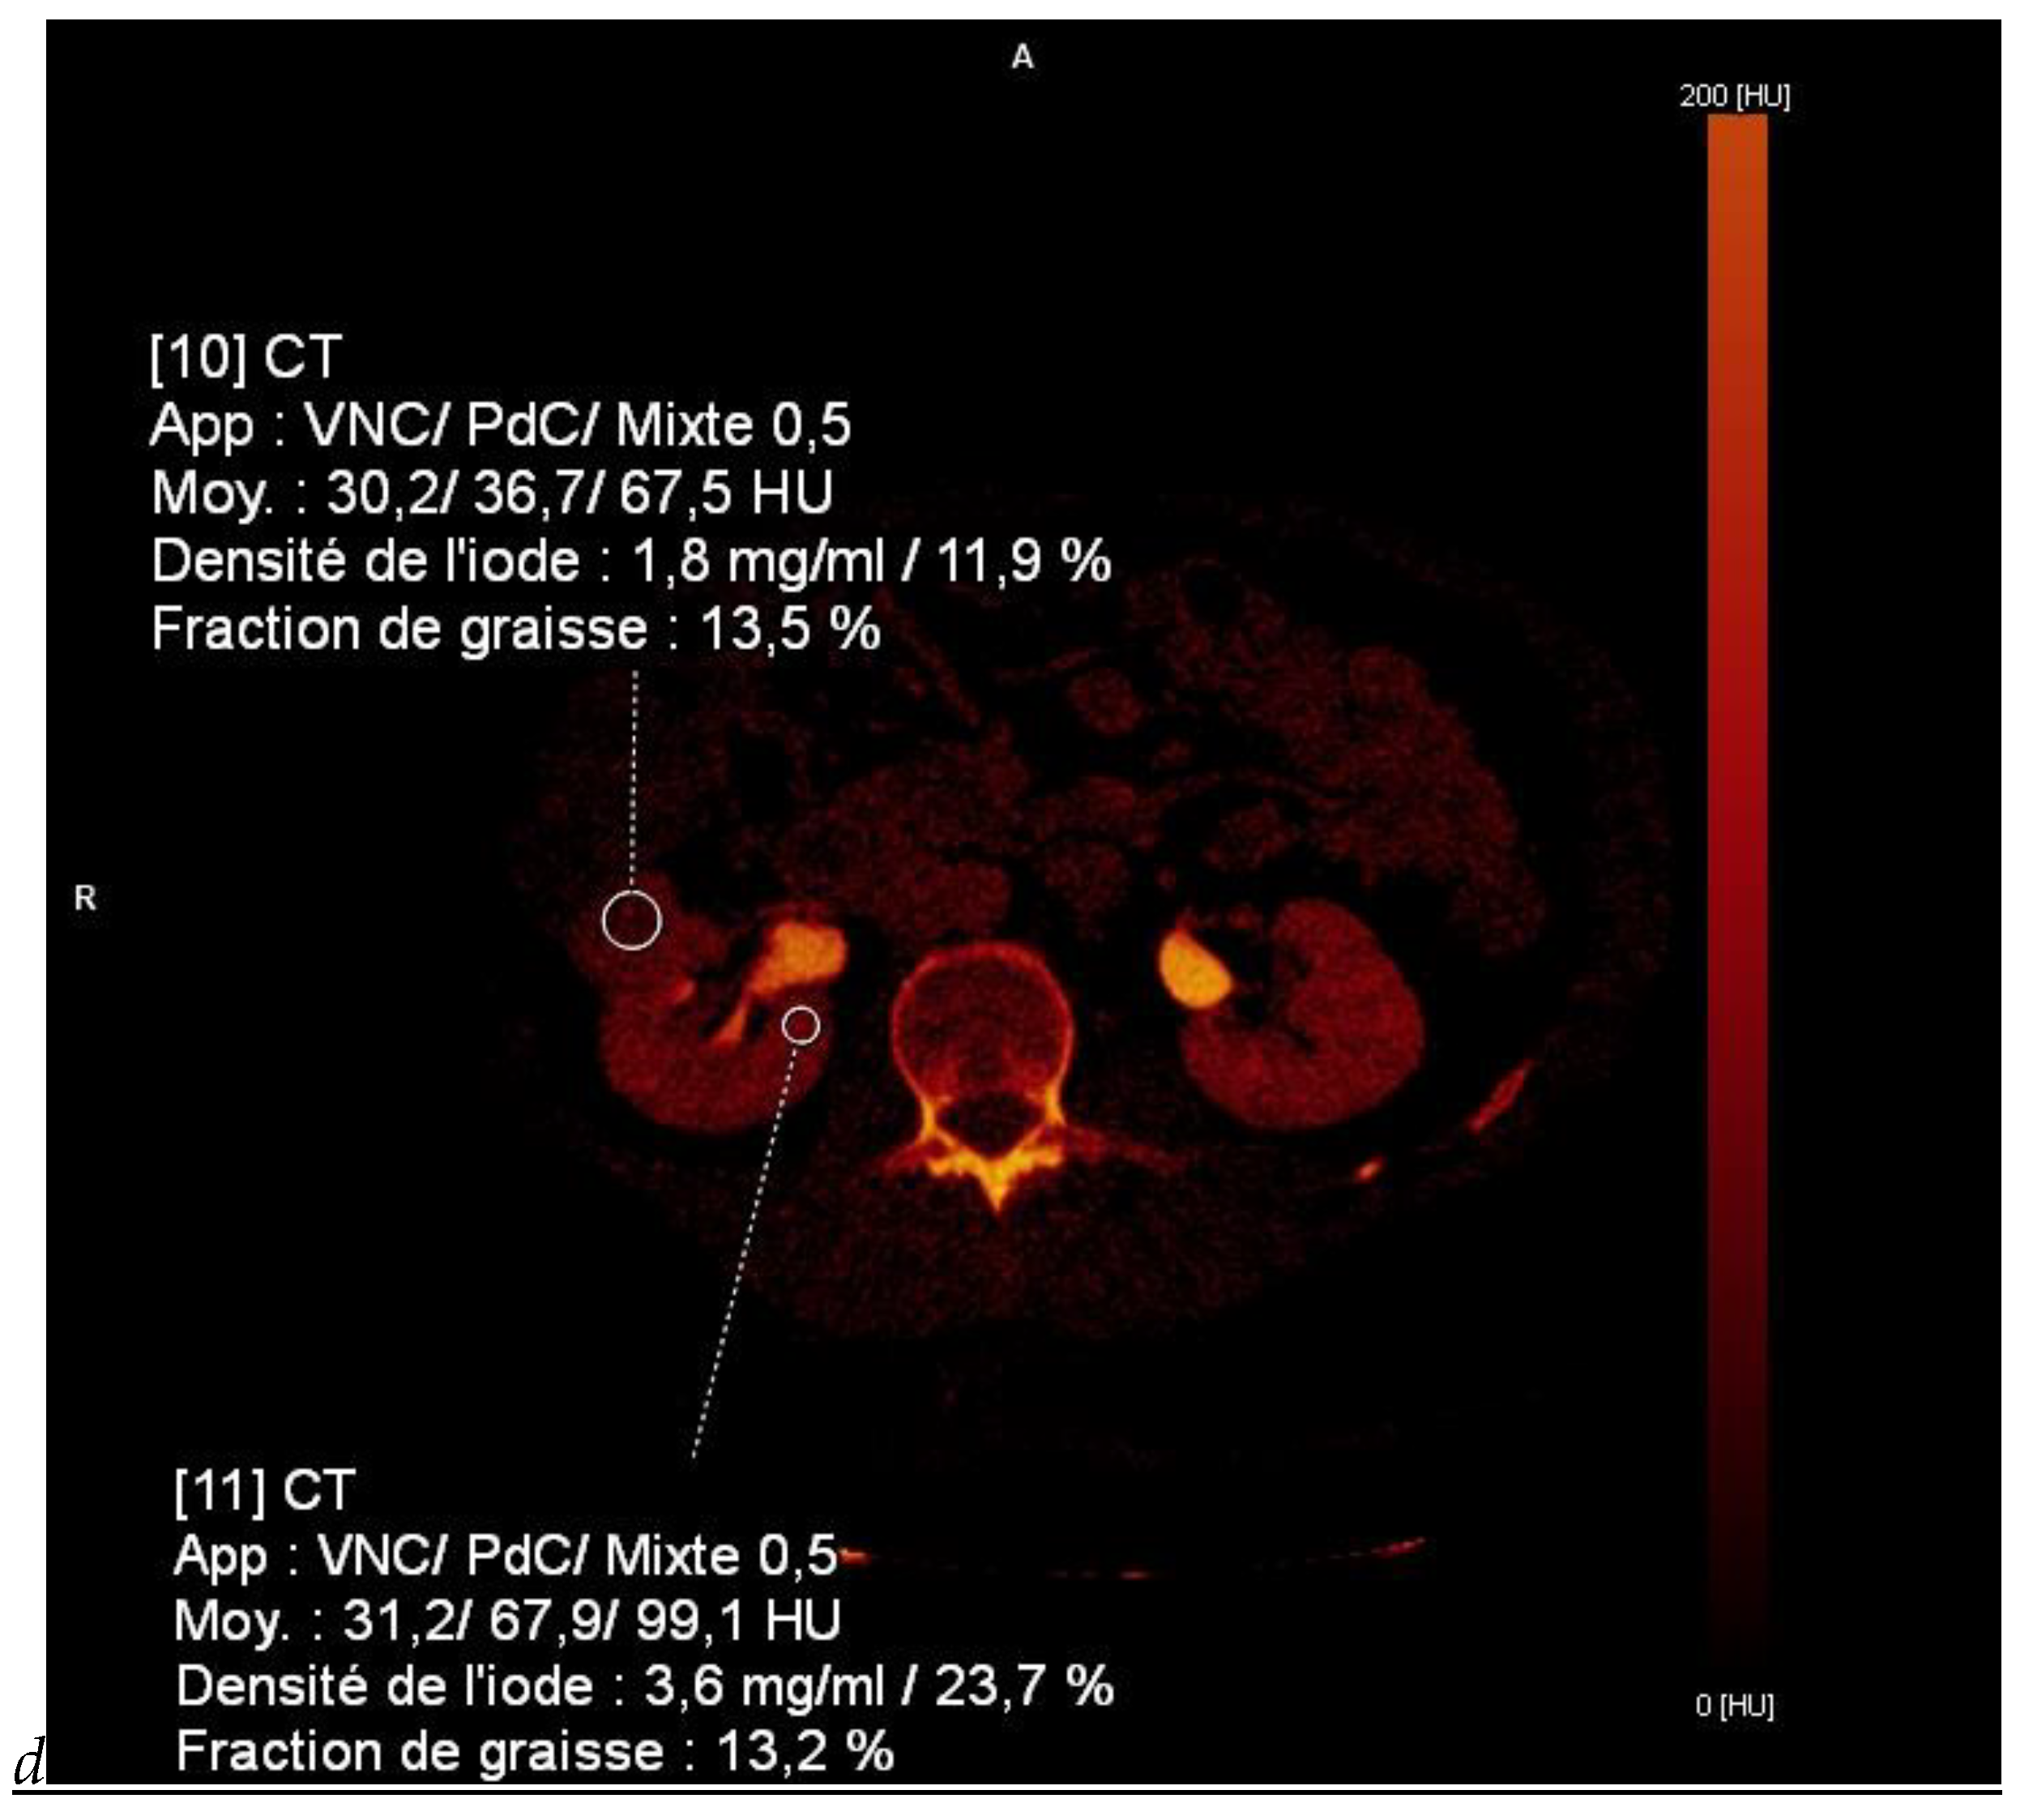

Figure 1.

Dual-energy CT aspect of a hypervascularized clear cell renal cell carcinoma of the upper pole of the right kidney. (a) Virtual unenhanced image. Note the presence of a solid exophytic renal mass in the upper pole of the right kidney. (b) The lesion enhances during the corticomedullary phase; measurement of the iodine concentration of the lesion (4.9 mg/mL) compared to that of the renal cortex (4.2 mg/mL) during the corticomedullary phase. (c) Monoenergetic image obtained at 40 keV during the nephrographic phase. Note the decrease in iodine concentration of the lesion (4.42 mg/mL) compared to that of the renal cortex (6.1 mg/mL). (d) Monoenergetic image obtained at 70 keV during the excretory phase. Compared to the monoenergetic image at 40 keV, the contrast between the lesion and the adjacent renal cortex is reduced. Note the washout of the lesion (iodine content: 1.8 mg/mL).

- DECT offers the possibility to obtain a direct quantification of the iodine concentration (in mg/mL) in a lesion, which represents a new option for the characterization of renal masses with equivocal enhancement, especially those with an attenuation baseline between 20 and 70 HU on unenhanced images [32,33]. They may represent either hyperdense cysts or hypovascular true enhancing tumors such as papillary RCC. In these patients, iodine quantification provides a more direct estimate of tumor blood supply and neoangiogenesis.

- Quantification of iodine concentration is also of interest for re-evaluation after treatment. Dual-energy iodine quantification could be adopted as an imaging biomarker of tumor viability in cases of advanced RCC treated with targeted or antiangiogenic therapies that reduce tumor perfusion with a limited effect on tumor size [17,30,34].